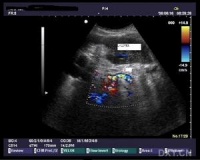

5.B超检查提示胆总管扩张、胆管内有结石。

3.B型超声波检查虽然价廉无创,对胆囊结石的准确率达98%,但因受十二指肠等空腔脏器的影响,对胆总管结石的准确率仅为50%左右,特别对十二指肠后段胆管难以显示。假阳性及假阴性率均较高。